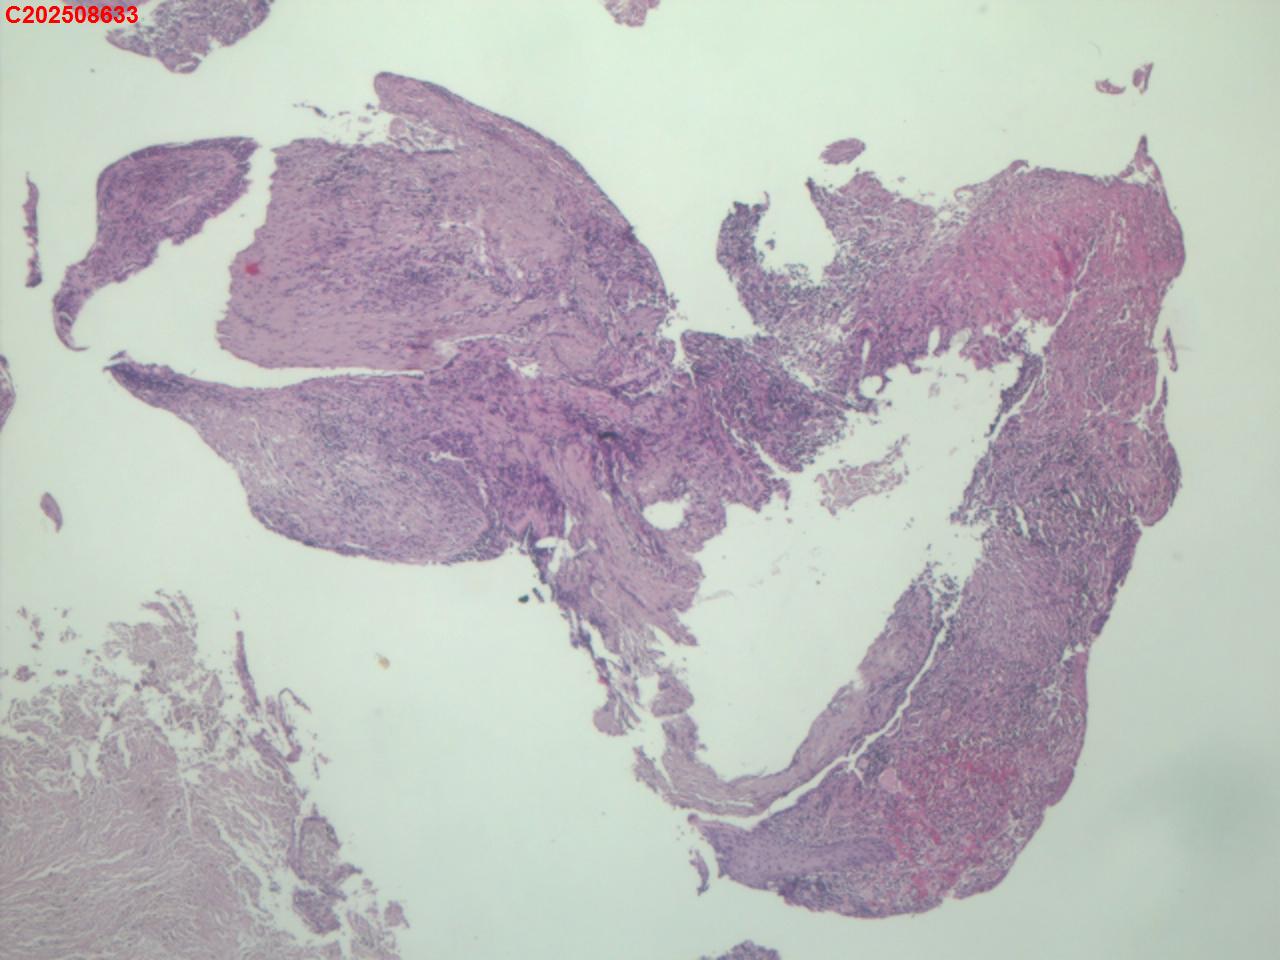

性别年龄82岁临床诊断肺结核?肿瘤?肺部感染?

一般病史2025-07-24 CT检查:考虑右肺上叶炎症伴肺实变,右肺上叶前段支气管显示不明确,建议治疗后复查或支气管镜检查。纵膈多发淋巴结增大。右侧胸腔积液。

标本名称纤支镜咬检

大体所见2025-07-25 气管镜检查示:左侧主支气管、上叶、下叶及各段支气管未见异常。右侧主支气管未见异常。右侧中间段支气管可见碳沫沉积。右肺上叶前段支气管开口可见脓苔附着,支气管开口狭窄,内可见灰黑色新生物阻塞右肺上叶前段支气管管腔。2025-07-25结核感染T细胞检测阳性。2025-07-27肺泡灌洗液查结核分枝杆菌复合群阳性。

坏死物比较多,没有看到明确的肿瘤性病变,可以考虑给一个描述性诊断。